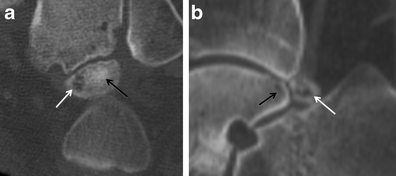

Bony sesamoiditis in a patient with plantar forefoot pain. Short axis PD (a) and T2-weighted fat-saturated (b) images reveal a mild asymmetric pattern of bone marrow oedema confined to the medial hallucal sesamoid. Note lack of oedema in the lateral hallucal sesamoid, first metatarsal head and surrounding soft tissues. Oblique sesamoid radiograph (c) shows no discernible abnormality. These results suggest bony sesamoiditis or stress reaction

Osteonecrosis. a Short-axis and sagittal CT images depict a fragmented medial hallucal sesamoid (black arrows), with increased density of the fragments (white arrows) which suggests post-traumatic osteonecrosis. b Short-axis and sagittal T2-weighted fat-saturated MRIs, and sagittal T1-weighted MRI obtained 1 month later show a pattern of severe bone marrow oedema (white arrows) with T1 hypointensity (black arrow) isolated to the medial hallucal sesamoid, and further collapse of the medial hallucal sesamoid, consistent with progression of osteonecrosis. Note normal marrow signal in the first metatarsal head (asterisks)